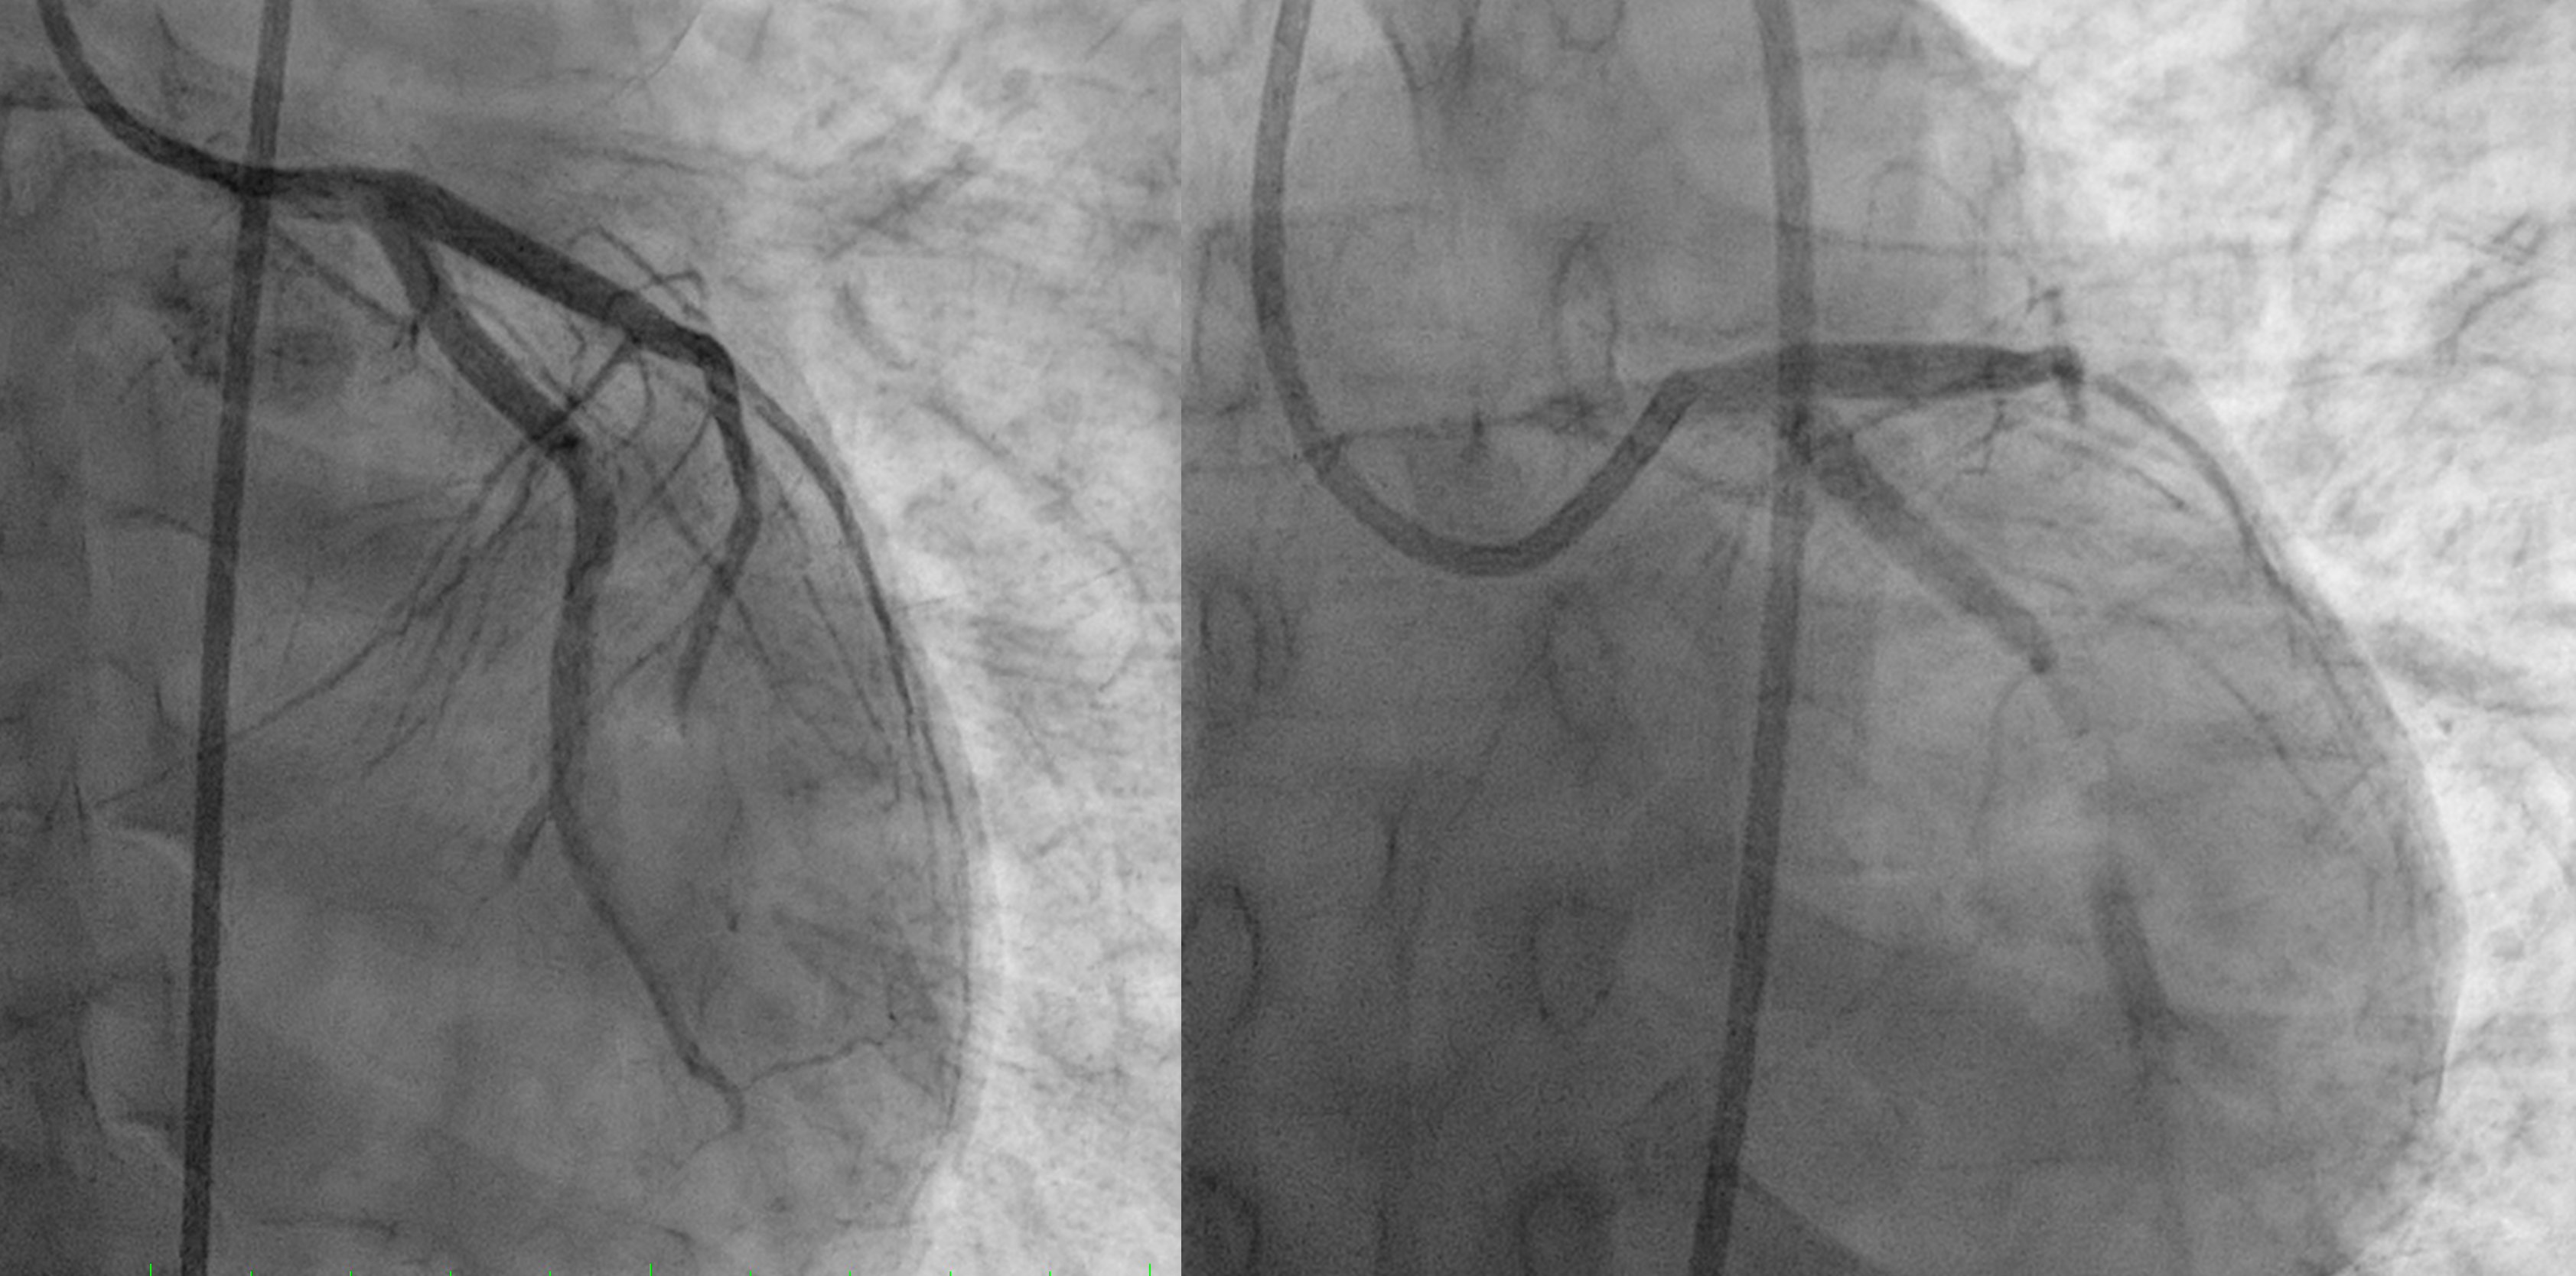

First patient was done thrombolytic therapy and failed, was done angiography with thrombus in LAD and LCx. We did thrombus aspiration and get TIMI 2 flow.Second patient was done primary PCI and having only POBA due to ambiguous distal LAD

first patient using Guidewire Runthrough to LAD and done Thrombus Aspiration and move to LCx to do Thrombus Aspiration. Patient was given eptifibatide bolus. But thrombus still high burden but already have better flow so we stopped case and heparinized. Second patient was having CTO LAD, wire with Pilot 50 but then escalated to Pilot 150. We could puncture the proximal cap, done POBA proximal with small balloon 1.5x15 mm and then up to 2.5x15 mm but the distal wire we suspect not in true lumenso we stopped the case after having better view distal LAD.